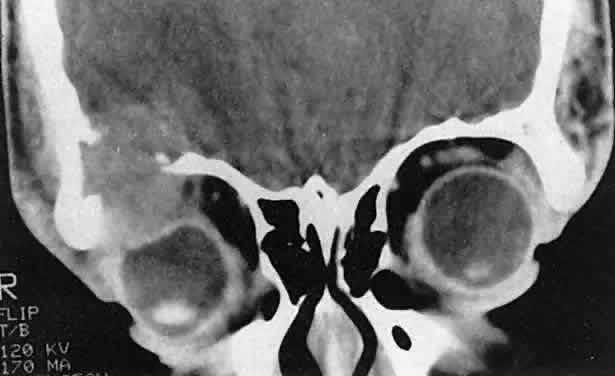

Orbital myositis may represent a greater proportion of cases of IIPT in childhood than in adulthood, and involvement of multiple extraocular muscles may occur more frequently in children than inadults. In orbital myositis, early diplopia and increased discomfort with attempted eye movement are typical symptoms. CT may show enlargement of one or more extraocular muscles in one or both orbits (Figs. 21 and 22). When a single muscle is involved, the specter of a primary or metastatic neoplasm within the muscle may be raised. However, external inflammatory signs, considerable pain and limited motility, and an explosive onset of symptoms within 24 hours all suggest orbital myositis. The uniform enlargement of the muscle, including its tendinous insertion (see Fig. 22), also helps distinguish the process from a neoplasm, which might be expected to produce a more focal, globular expansion. Echography may support the diagnosis of inflammation by showing edema in the episcleral space as a relative sonolucency between the scleral and orbital fat echoes (Fig. 23). Its CT counterpart is an increase in the radiodensity and thickness of the ocular tunica.

Fig. 21. A. This 16-year-old boy had acute onset of bilateral proptosis, pain, diplopia, chemosis, and conjunctival injection. B. Bilateral enlargement of the superior and medial rectus and inferior oblique muscles. Other sections showed similar involvement of other extraocular muscles.

Fig. 22. The uniform enlargement of the left medial rectus muscle, including its tendinous insertion, is characteristic of orbital myositis.